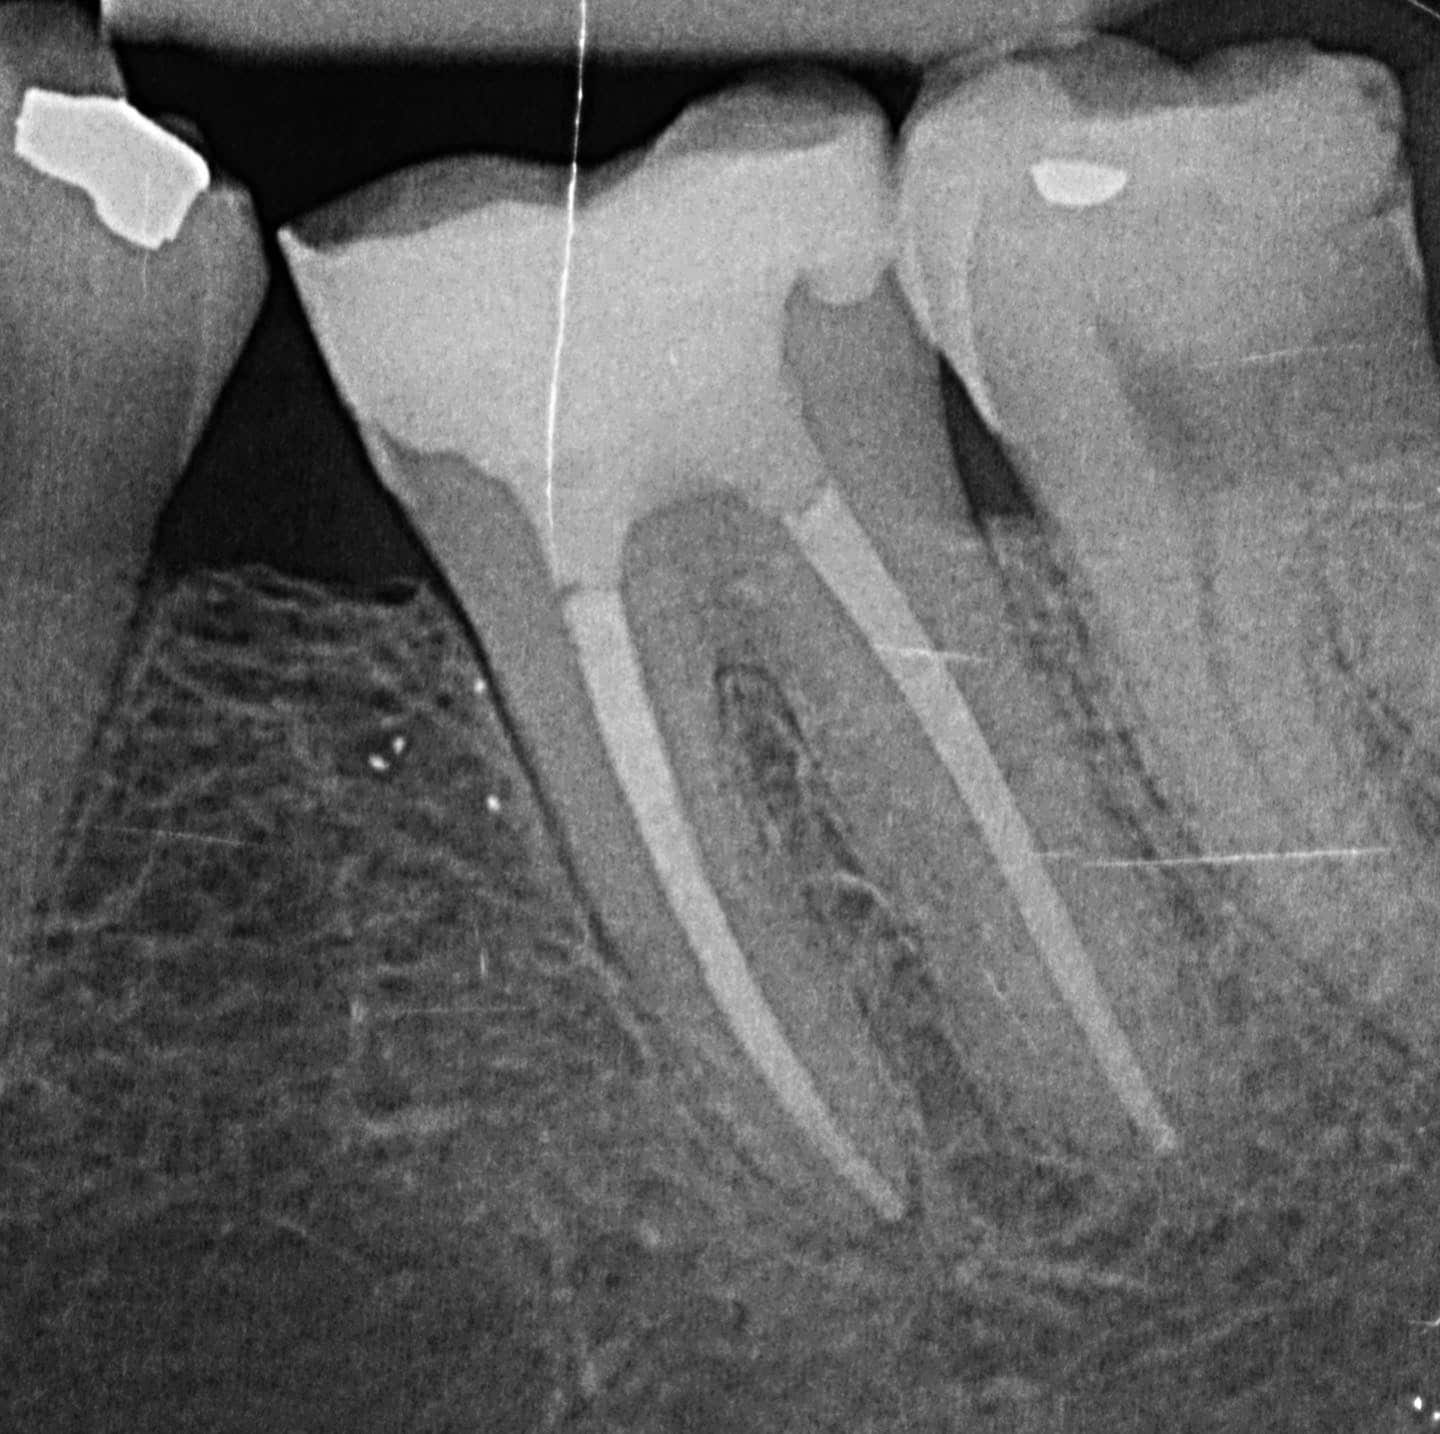

Moderne Diagnose- und Behandlungsverfahren: Einsatz digitaler Röntgentechnologie und elektrischer Längenmessung für genaue Diagnosen und erfolgreiche Behandlungschancen.

Mit modernster Technik und umfangreicher Erfahrung gewährleisten unsere Spezialisten eine präzise und effektive Wurzelkanalbehandlung.

Die Wurzelkanalbehandlung wird erforderlich, wenn das innere Gewebe des Zahnes, das sogenannte Pulpa, infiziert oder entzündet ist. Unbehandelt führt dies zu Schmerzen und kann zum Zahnverlust führen.